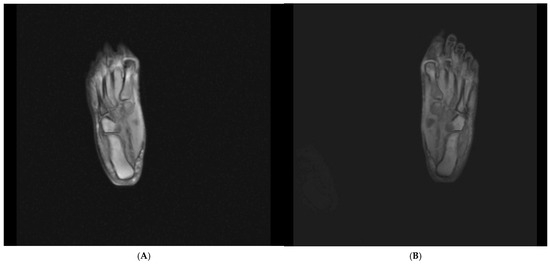

A 42-year-old female patient (height, 160 cm; weight, 74 kg) sought physiotherapy treatment because of pain that had developed in her left foot 2 years prior. Imaging revealed enthesitis at the point where the plantar fascia attached to the calcaneus (Figure 1). At the level of the second and third metatarsophalangeal joints, there was a soft-tissue density consistent with a Morton’s neuroma measuring approximately 6 × 2 mm (long axis: 6 mm, short axis:2 mm) in diameter. A magnetic resonance imaging scan of the right foot taken 1 year later showed minimal fluid accumulation posteriorly at the level of the talocalcaneal joint. At the level where the plantar fascia attached to the base of the calcaneus, there was an increase in density and thickness owing to soft-tissue edema. At this level, the plantar fascia thickness was measured at approximately 4 mm, and the density had increased.

Figure 1.

(A) Radiograph of the right foot. (B) Radiograph of the left foot.